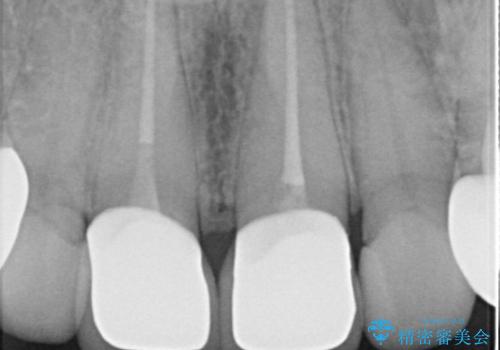

- 他院で1年ほど前にセラミッククラウンを入れたそうですが、しばらくしてから歯茎から膿が出てきたそうです。

歯髄診にて歯髄が失活していることが判明したため、クラウンを除去し根管治療を行ってから、再度オールセラミッククラウンを作成しています。

今回のケースはクラウン除去した際に露髄点は認められなかったため、形成時の発熱が原因であったと推測しています。